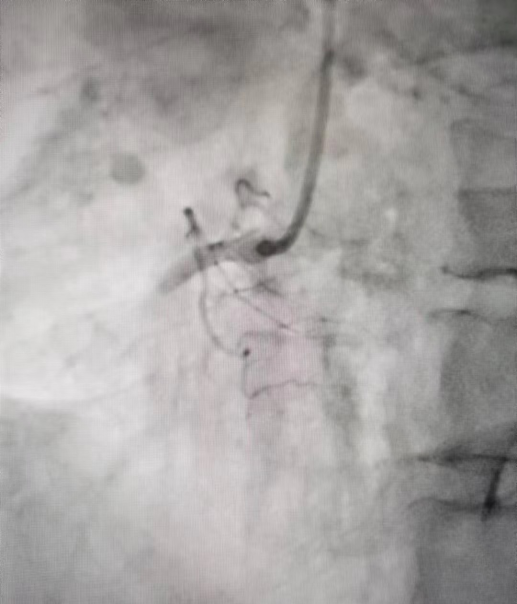

术前造影